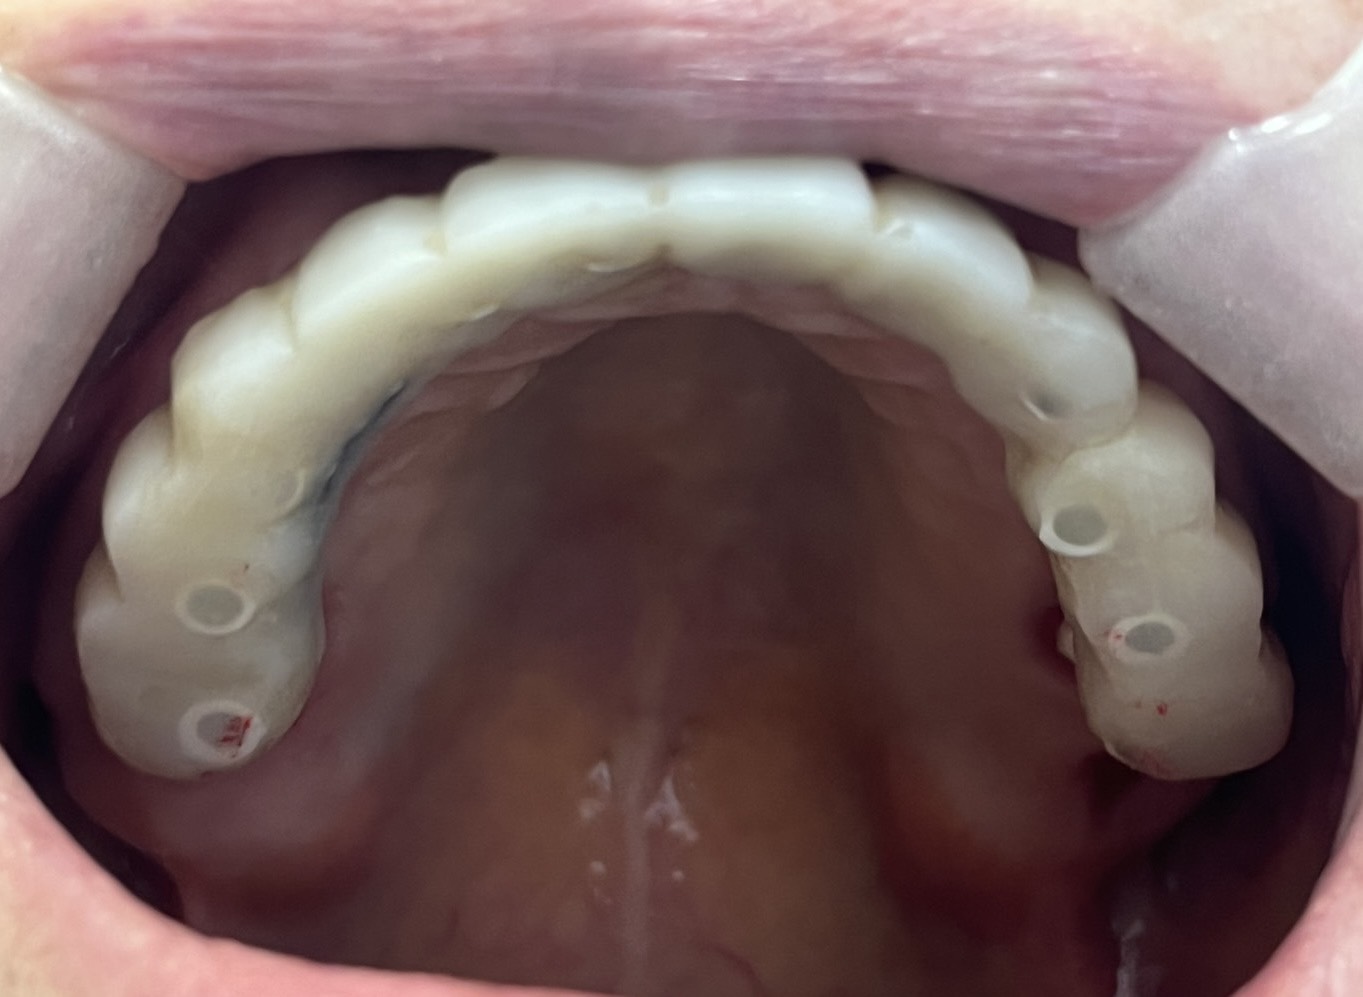

一位患者特地從外州飛到拉斯維加斯,評估後當天決定進行全口植牙。整個療程不到兩小時,即拔即植即固定臨時牙。

手術當天完成全口掃描,四個月後更換為最終固定假牙。這段期間,患者維持良好的生活品質,醫師也能安心照護,不用每天提心吊膽、接不完病患來電。

不需要全身麻醉,或者是舒眠麻醉的情況之下,就完成與自然牙排列相仿全口重建。不用擔心歪斜長長的植體打到顴骨或眼睛。